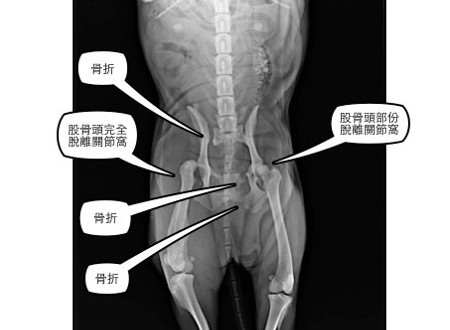

斷腿十三出院囉,多樣義賣商品募集醫療費中